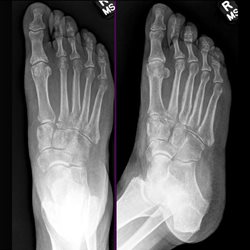

Various foot cases